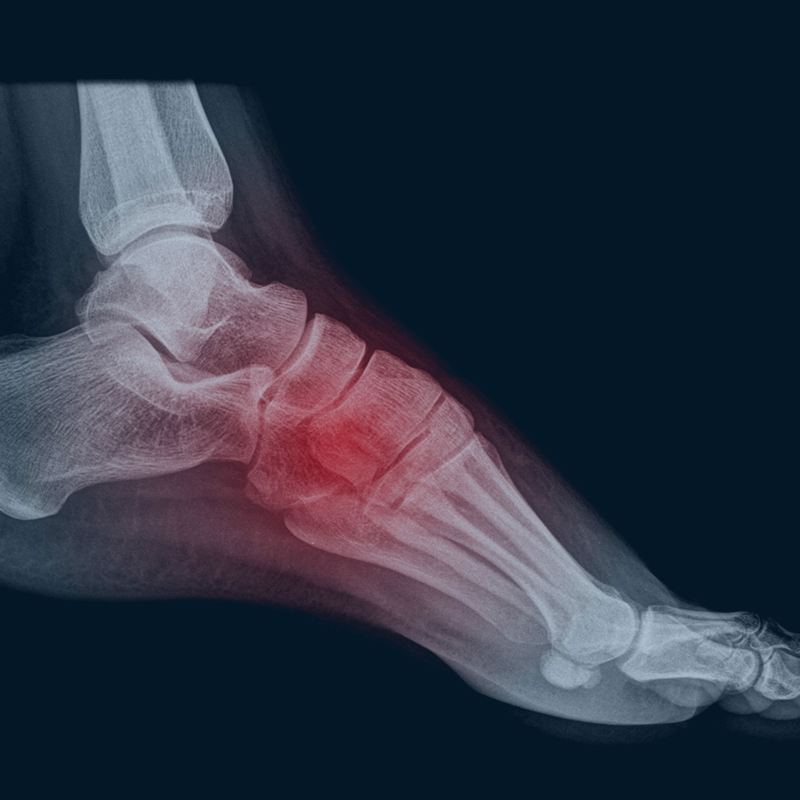

Where Do You Feel Pain? Click for a List of Possible Causes